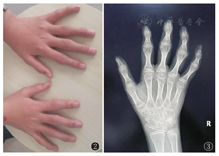

四肢关节:本组14例患儿均存在双手近端指间关节肿胀(图2),食指及中指显著,其中存在手关节活动受限7例;膝关节受累11例,2例膝内翻、1例膝外翻,关节膨大8例,无明显关节肿胀、疼痛及活动受限。

X线及CT检查:14例患儿影像学检查均存在异常,各部位X线检查均可见骨密度降低。长骨及手:干骺端明显膨大,其中以食指、中指掌指关节及近端指间关节远端受累显著(图3)。掌骨、指骨干骺端膨大14例、腕关节干骺端膨大7例、膝关节干骺端膨大8例;关节间隙狭窄6例,骨骺提前闭合及骨龄提前7例。骨盆平片表现为双髋关节间隙狭窄11例,股骨头骨骺扁平8例(图4A),股骨颈变短2例、股骨头外移4例,关节面硬化、囊变、骨质破坏8例。脊柱:椎体普遍变扁,上下缘形态不规则、前上下缘可见骨质缺损,椎间隙变窄、中后部明显,椎弓根变短(图5);颈椎受累1例,胸、腰椎受累13例。